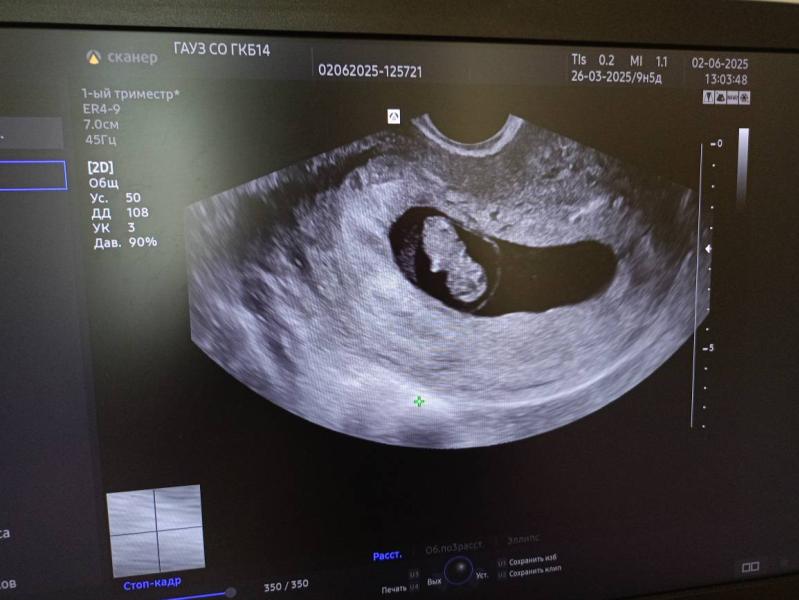

В понедельник 2ого июня я была на УЗИ и на приеме.

Начну пожалуй с УЗИ ( это было мое второе УЗИ, первое было на сроке 4-5 недель , тогда я только узнала о тебе и на следующий же день поехала на первое УЗИ 😅

По узи всё хорошо, срок беременности 9.1 день по малышу🤰Ручки и ножки только образовываются, скоро он будет полноценным человечком😍( Расти малыш!). Малыш прекреплен по задней стенке , я уверена, что он мальчик , сынок!

На фото второе и первое узи❤🔥